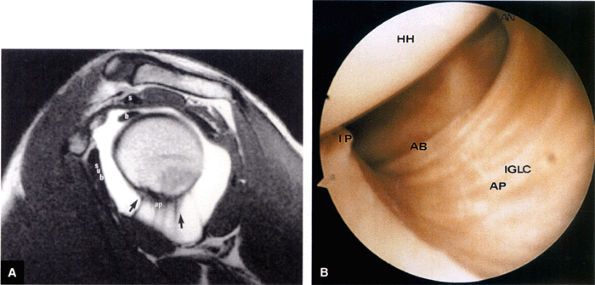

FIGURE 8.80 ● (A) The axillary pouch of the IGHL is seen on a T1-weighted sagittal MR arthrogram. Arrows and ap, axillary pouch of IGHL; b, biceps tendon; s, supraspinatus tendon; sub, subscapularis tendon. (B) The IGHL complex. An arthroscopic photograph shows the anterior band (AB) and axillary pouch (AP) components of the inferior glenohumeral ligament (IGL) complex. The inferior pole of the glenoid (IP) and the anatomic neck attachments of the IGL complex (AN) are shown as viewed from the axillary pouch. HH, humeral head.

FIGURE 8.81 ● (A) The anterior band (ab) and posterior band (pb) of the IGHL (curved arrows) extend from the glenoid origin to the humeral attachment, as seen on an enhanced T1-weighted sagittal (oblique) image. C, coracoid; H, humeral head. (B) On a gross shoulder specimen, the superior course of the anterior band (AB) of the IGHL is identified (triangular marker). The glenoid (G) and humeral head (HH) are also identified.

FIGURE 8.82 ● A gross shoulder specimen illustrates the structure of the inferior glenohumeral ligament (IGL) complex. With abduction of the humerus, the IGL structures are more prominent and taut in position. Coronal oblique MR images routinely show the lax axillary pouch of the IGL when the humerus is in the adducted position. Curved arrow, axillary pouch; AB, anterior band; AL, anterior labrum; HH, humeral head; PB, posterior band; PL, posterior labrum.